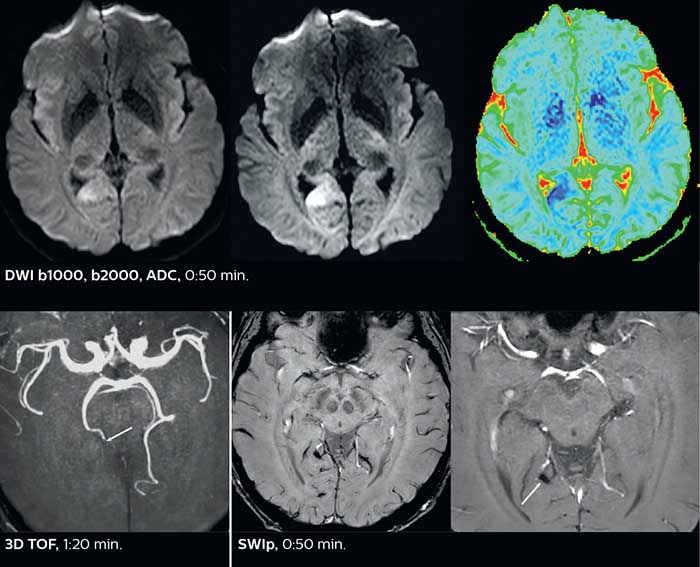

Fast acute stroke protocol

This is an example of acute ischemic stroke with distal occlusion of the right posterior cerebral artery. Note the improved visibility of the ischemic territory on the diffusion weighted image with high b-value. The 3D FLAIR shows a distal PCA occlusion. The fast SWIp depicts the thrombus on the isolated second echo image. The total scan time (including SmartBrain, preparations and a fast 3D T1w TSE Gd) is 8:00 minutes.

The ability to perform more sequences can help in making a swift and confident diagnosis. “For example, our stroke cases usually include the regular sequences that every center does (b1000 diffusion, FLAIR, time-of-flight angiography), but we also image supra aortic vessels, and we can replace a gradient echo sequence with a fast 50-second susceptibility-weighted sequence, and all of this doesn’t add much time. because all the regular sequences are accelerated on Elition.”

“The time savings with Compressed SENSE and MultiBand SENSE make it easier to add sequences to give us additional insights. Depending on the context and the first results, we might add a DSC perfusion to assess the ischemic penumbra, an ASL perfusion to help find an alternative cause in case of normal diffusion, or add a high-resolution T1 sequence for a stroke patient, to quickly assess wall imaging in emergency cases. The additional sequences can help improve patient management, because we can already consider some alternative diagnoses if the morphological MRI is normal.”

Improved diffusion imaging in stroke patients

Using MultiBand SENSE allowed the staff to improve their diffusion quality. “Our diffusion sequence was already fast before, about 40 seconds. Now with Elition, it still lasts 40 seconds, but we improved the spatial resolution by 0.2 mm and use high b-values to be more sensitive to visualize changes related to acute stroke,” says Dr. Savatovsky.